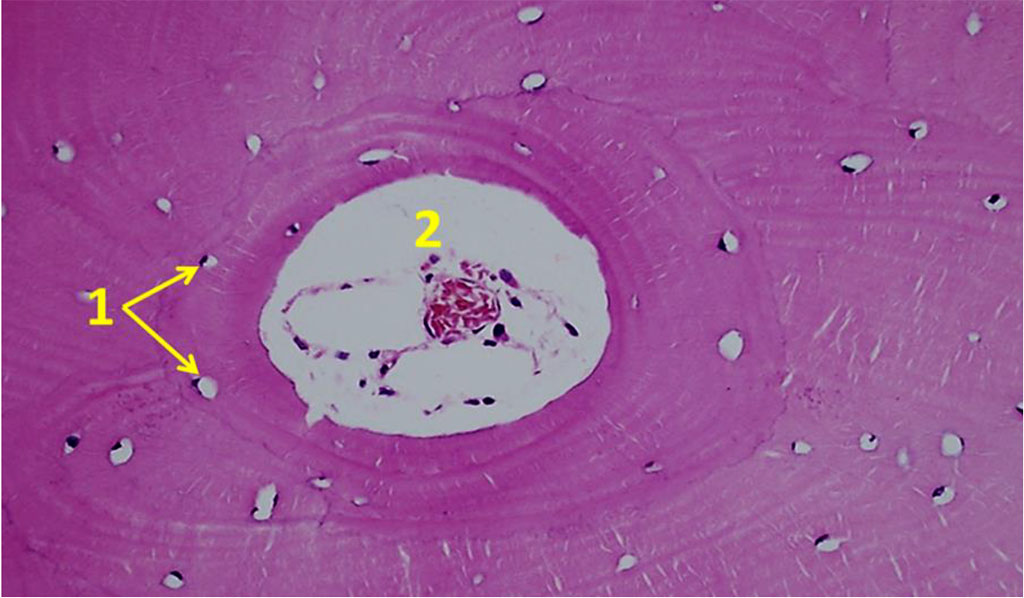

Osteocytes from the chin symphysis area are oriented along the bone plate course, whereas osteocytes from the outer oblique line area – along the circles around the Haversian canals (Fig. 10).

Figure 10. Orientation of osteocytes in relation to the Haversian canals on histological preparations of the intact bone from the chin symphysis area (×100; hematoxylin-eosin staining; 1– osteocytes; 2 – Haversian canals).

The histological structure of the bone biopsy obtained from the maxillary tuberosity area differed from what could be observed in the biopsies taken from the chin symphysis area and of the mandible outer oblique line, the difference being obvious through the vertical trabeculae arrangement, the fine-meshed structure of the spongy substance, and the orientation of the bone plates along the concentric circles around the Haversian canals (Fig. 11).

Figure 11. Orientation of osteocytes in relation to the Haversian canals on histological preparations of the intact bone from the maxillary tuberosity area (×100; hematoxylin-eosin stain; 1– osteocytes; 2 – Haversian canal).